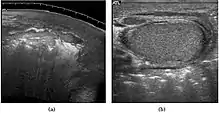

At ultrasound, the findings of acute epididymitis include an enlarged hypoechoic or hyperechoic (presumably secondary to hemorrhage) epididymis [Fig. 20a]. Other signs of inflammation such as increased vascularity, reactive hydrocele, pyocele and scrotal wall thickening may also be present. Testicular involvement is confirmed by the presence of testicular enlargement and an inhomogeneous echotexture. Hypervascularity on color Doppler images [Fig. 20b] is a well-established diagnostic criterion and may be the only imaging finding of epididymo-orchitis in some men.

Doppler ultrasound of epididymitis, seen as a substantial increase in blood flow in the left epididymis (top image), while it is normal in the right (bottom image). The thickness of the epididymis (between yellow crosses) is only slightly increased (7 mm).

Doppler ultrasound of the scrotum of the same case, in the axial plane, showing orchitis (as part of epididymo-orchitis) as hypoechogenic and slightly heterogenic left testicular tissue (right in image), with an increased blood flow. There is also swelling of peritesticular tissue.